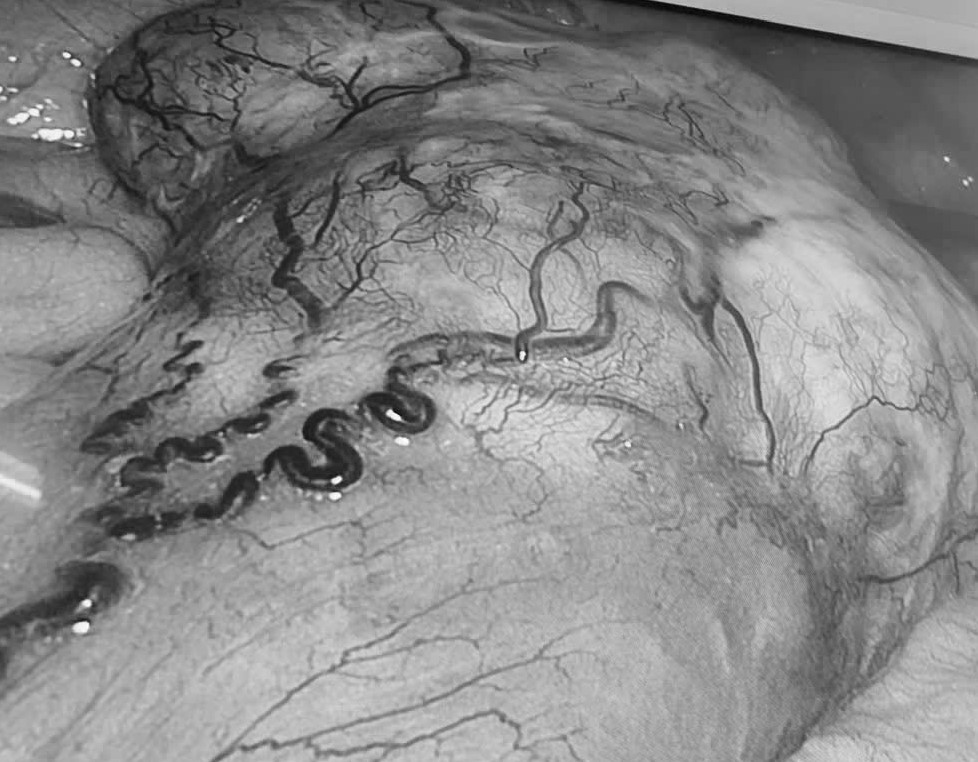

Hình ảnh U GIST qua màn hình nội soi. Ảnh: BVCC.

Tại Khoa Ngoại Tổng quát, Bệnh viện Đa khoa Vĩnh Long, bệnh nhân được các bác sĩ khai thác bệnh sử chi tiết, thăm khám lâm sàng kỹ lưỡng, đồng thời chỉ định thực hiện các cận lâm sàng chuyên sâu: Nội soi đại tràng ghi nhận tổn thương u sùi, gây hẹp lòng đại tràng, hình ảnh nghi ngờ ác tính. Chụp CT-scan ổ bụng phát hiện thêm một khối u đặc vùng hạ vị kích thước khoảng 10 x 10 cm, xuất phát từ ruột non, hình ảnh gợi ý u mô đệm đường tiêu hóa (GIST).